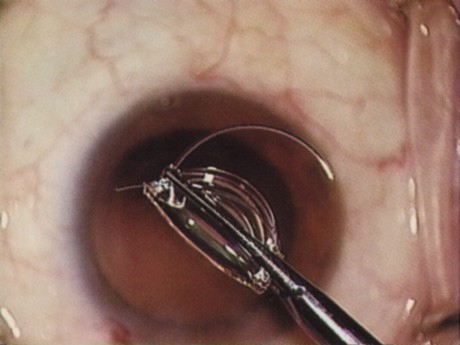

HYDRODISSECTION Hydrodissection can be performed after the surgeon has successfully completed capsulorrhexis.97 If the capsulorrhexis is not intact, fluid forced around the interior of the capsule may cause the bag to splay open. With capsulorrhexis, hydrodissection is a safe and extremely useful maneuver. Hydrodissection can be thought of as two maneuvers: hydrodelineation and cortical cleaving hydrodissection. By placing a 27-gauge cannula on a syringe filled with balanced saline solution (BSS), the surgeon can direct fluid beneath the residual anterior capsular rim to create a cleavage plane. Depending on the direction the fluid wave takes, different lamellae of the cataract will be separated. Hydrodelineation is the term used when the cleavage plane separates the adult nucleus from the fetal nucleus or the adult nucleus from the more peripheral epinucleus. Hydrodelineation often results in the characteristic golden ring sign (Fig. 11). Cortical cleavage occurs when the cortex is separated from the capsular bag (Fig. 12). Finding the cortical cleavage plane may be facilitated by gently lifting the capsular margin away from the cortex with the BSS cannula before injecting. Several small bursts of fluid allow the surgeon to monitor progress of the fluid wave. When dealing with a soft nucleus, the authors strive to perform true cortical cleaving hydrodissection. For a hard nucleus, hydrodelineation allows manipulation of less of the nuclear bulk, although the remaining epinuclear shell must be addressed in an additional step. Hydrodelineation is particularly useful if the nucleus is not freely mobile after cortical cleaving hydrodissection.